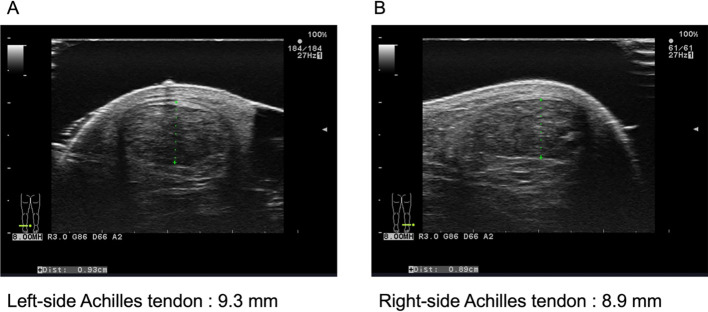

Familial hypercholesterolemia (FH), a genetic disorder characterized by the early onset of coronary artery disease, is found in one of 300 people. In the 2022 Japanese FH guidelines, a cut-off value for Achilles tendon thickness measured using ultrasound has been added, enabling the diagnosis of FH during a Workers' Compensation Insurance Secondary Health Examination. In individuals for whom the possibility of FH could not be ruled out based on low-density lipoprotein cholesterol levels, we measured the Achilles tendon thickness by ultrasound and found four cases of FH. The detection of FH in asymptomatic workers is crucial for long-term cardiovascular risk management.